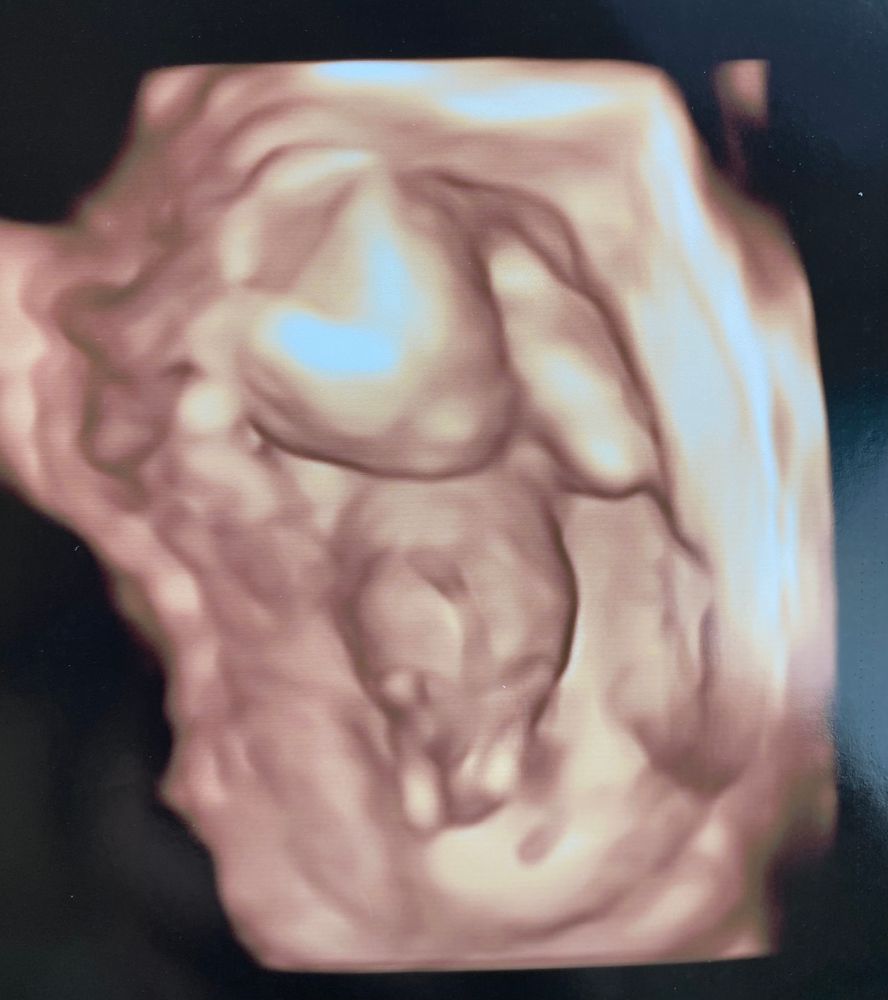

Гадаем пол 🙈

Девочки, всем спасибо за ответы!) у нас девочка 😍

Просто интересно 🤔😁 Наш пирожок :)) 16 недель